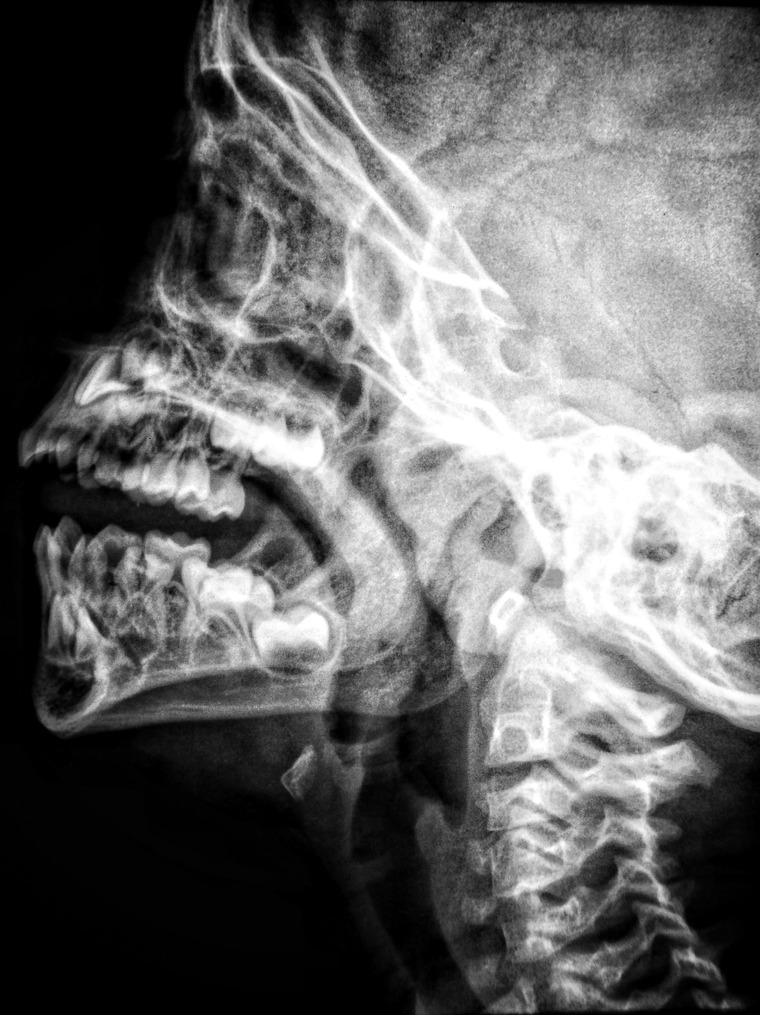

Pladsmangel

Hvis der ikke er plads i kæben, kan visdomstanden skubbe til de andre tænder eller blive klemt nede i knoglen.

Mindre rødder

På unge tænder er rødderne ofte ikke fuldt udvoksede endnu. Det mindsker risikoen for at ramme nervebaner i kæben.